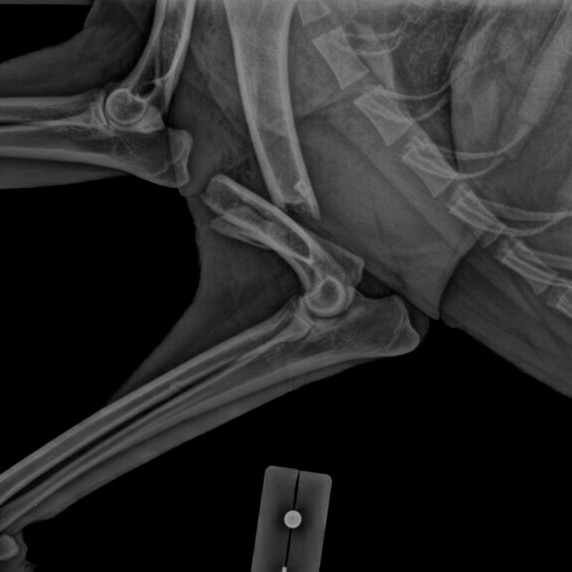

La traumatología y la ortopedia son las ramas de la medicina que se ocupan de las lesiones del aparato locomotor.

Se ocupan de las fracturas y luxaciones de los huesos, de las lesiones de ligamentos y tendones, tumores óseos y problemas de la columna vertebral como las hernias discales.

La ortopedia se centra en corregir las patologías o deformidades no provocadas por un traumatismo, por ejemplo las displasias.

Las lesiones que tratamos comúnmente son traumáticas (provocadas por un golpe), pero también las hay congénitas (de nacimiento) o adquiridas (debidas a enfermedades o lesiones no traumáticas).